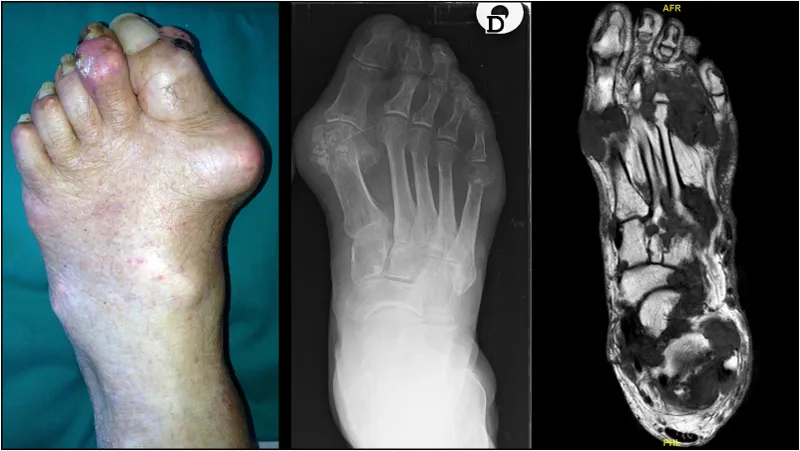

- Specific Patterns:

- RA: Symmetrical JSN, marginal erosions, osteopenia.

- Gout: "Rat-bite" erosions (punched-out), tophi.

- PsA: "Pencil-in-cup" deformity, periostitis.

- Advanced Imaging (if needed):

- MRI: Early cartilage/soft tissue changes, bone marrow edema.

- CT: Detailed bone anatomy, pre-op planning.